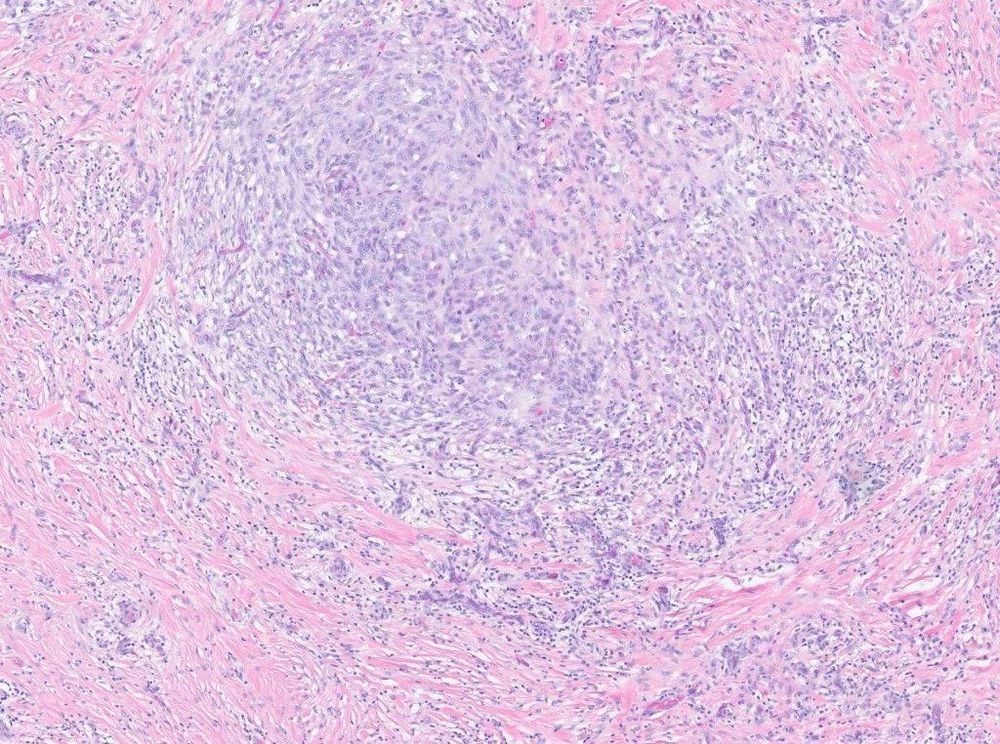

#PathSky Laryngeal mass, older adult male. Primitive, highly vascular round cell neoplasm for the most part.

This is classic morphology for a GLI1 coamplified differentiated liposarcoma with perineurial-like whorls. So now the MDM2 amplification makes sense. The current tumor is showing essentially classical features of a GLI1 amplified soft tissue sarcoma. So the morphology/molecular explain each other.

A big panel of IHC was negative. For somewhat unclear reasons, MDM2 FISH was ordered and was amplified. Does this make any sense?

Well, it turned out he had a tumor in the same laryngeal location a few years ago, diagnosed as a “fibroinflammatory lesion with some features of IgG4 disease”.